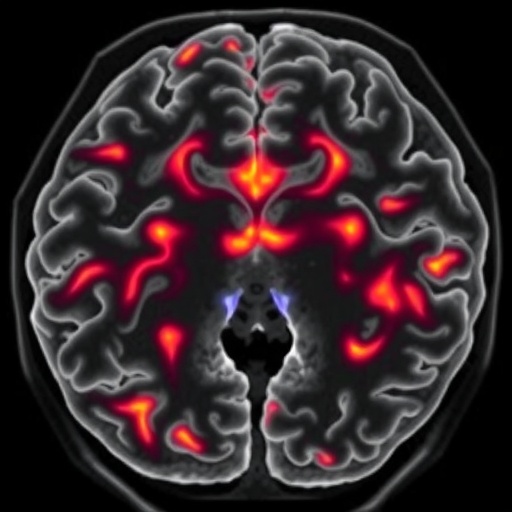

One of the standout features of this research is its comprehensive approach to patient assessment. By utilizing advanced imaging techniques, including MRI and CT scans, the authors present intricate details that allow for a keen differentiation between DLGMT and other similar entities. The radiological presentation of these tumors is not only pivotal for initial diagnosis but also for ongoing management strategies. As radiologists and clinicians continue to refine their diagnostic frameworks, the novel imaging characteristics highlighted in this study could serve as a guide, minimizing the likelihood of misdiagnosis.